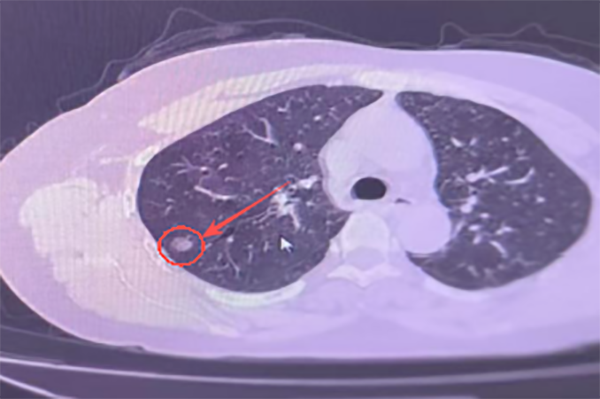

△ 患者CT影像

张阿姨(化名)近期在体检时发现右肺上叶有一个结节,放心不下的她决定到南通六院胸外科寻求进一步诊治。经CT诊断“右肺上叶孤立性肺结节”,大小为10mm×9mm。

虽然结节体积不大,但因为处于肋骨及肩胛骨下方,位置较为刁钻。如果使用传统定位术式需反复穿刺穿过骨头,患者疼痛明显且可能因遮挡导致定位失败;术中触摸定位更是“大海捞针”定位难度大、风险高、并发症多。